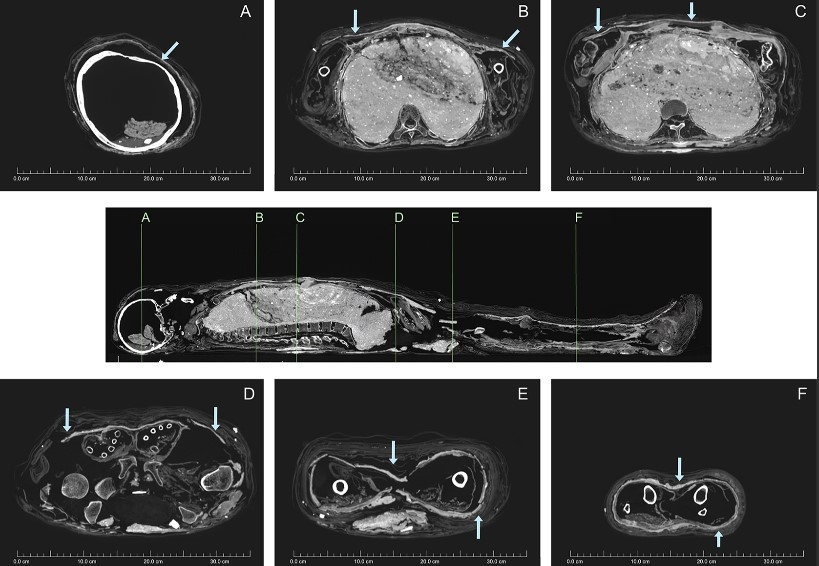

Các nhà khoa học Australia mới tiến hành chụp CT và xác định niên đại bằng phương pháp carbon phóng xạ cho một xác ướp Ai Cập và cỗ quan tài. Hiện chúng được lưu giữ và bảo quản tại Đại học Sydney.

Kết quả kiểm tra cho thấy xác ướp người phụ nữ có niên đại vào khoảng năm 1200 trước Công nguyên.

Trong khi đó, chiếc quan tài chứa xác ướp có niên đại vào khoảng năm 1000 trước Công nguyên.

Điều này đồng nghĩa với việc chiếc quan tài và xác ướp có niên đại không trùng khớp. Thi hài người phụ nữ có niên đại lớn hơn cỗ quan tài khoảng 200 năm.

Từ đây, các chuyên gia suy đoán có thể một tay lái buôn đã đặt xác ướp người phụ nữ vào quan tài có niên đại thấp hơn để bán được với giá cao.

Do đó, quan tài có khắc tên một người phụ nữ là Meruah không phải là danh tính thực sự của xác ướp đặt bên trong.

Dù các chuyên gia chưa tìm ra danh tính thực sự của người phụ nữ này nhưng các chuyên gia biết được rằng, người này qua đời khi khoảng 26 - 35 tuổi.

Xác ướp người phụ nữ này được bọc trong một lớp bùn. Kỹ thuật này được cho là bắt chước theo phong tục mai táng của hoàng gia Ai Cập thời cổ đại.